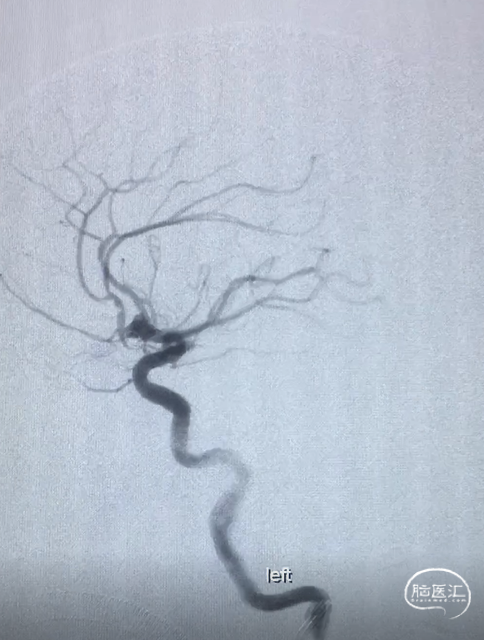

术前DSA:LICA正侧位及工作角度造影显示前交通动脉瘤